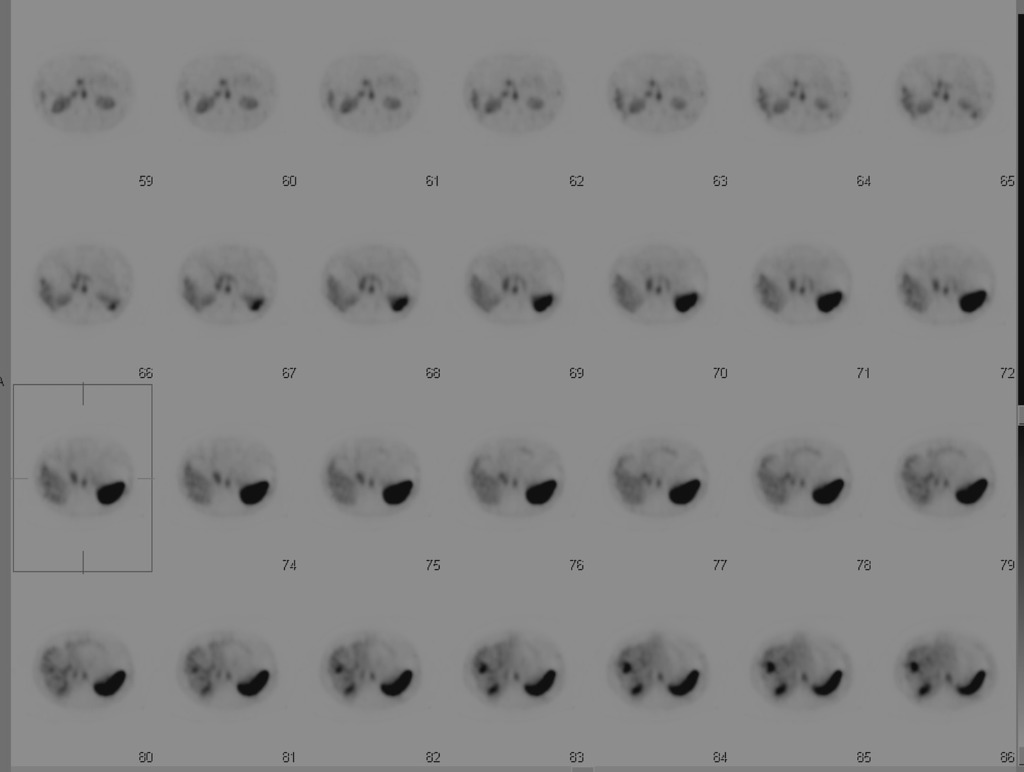

You think that the following is a hemangioma in a fatty liver, but the mid-level provider doesn’t believe you. The patient has abandoned pacer leads and can’t get an MRI. What is your next step?

Tagged RBC scan to look for hemangiomas

tagged RBC scan demonstrating hemangiomas in the liver